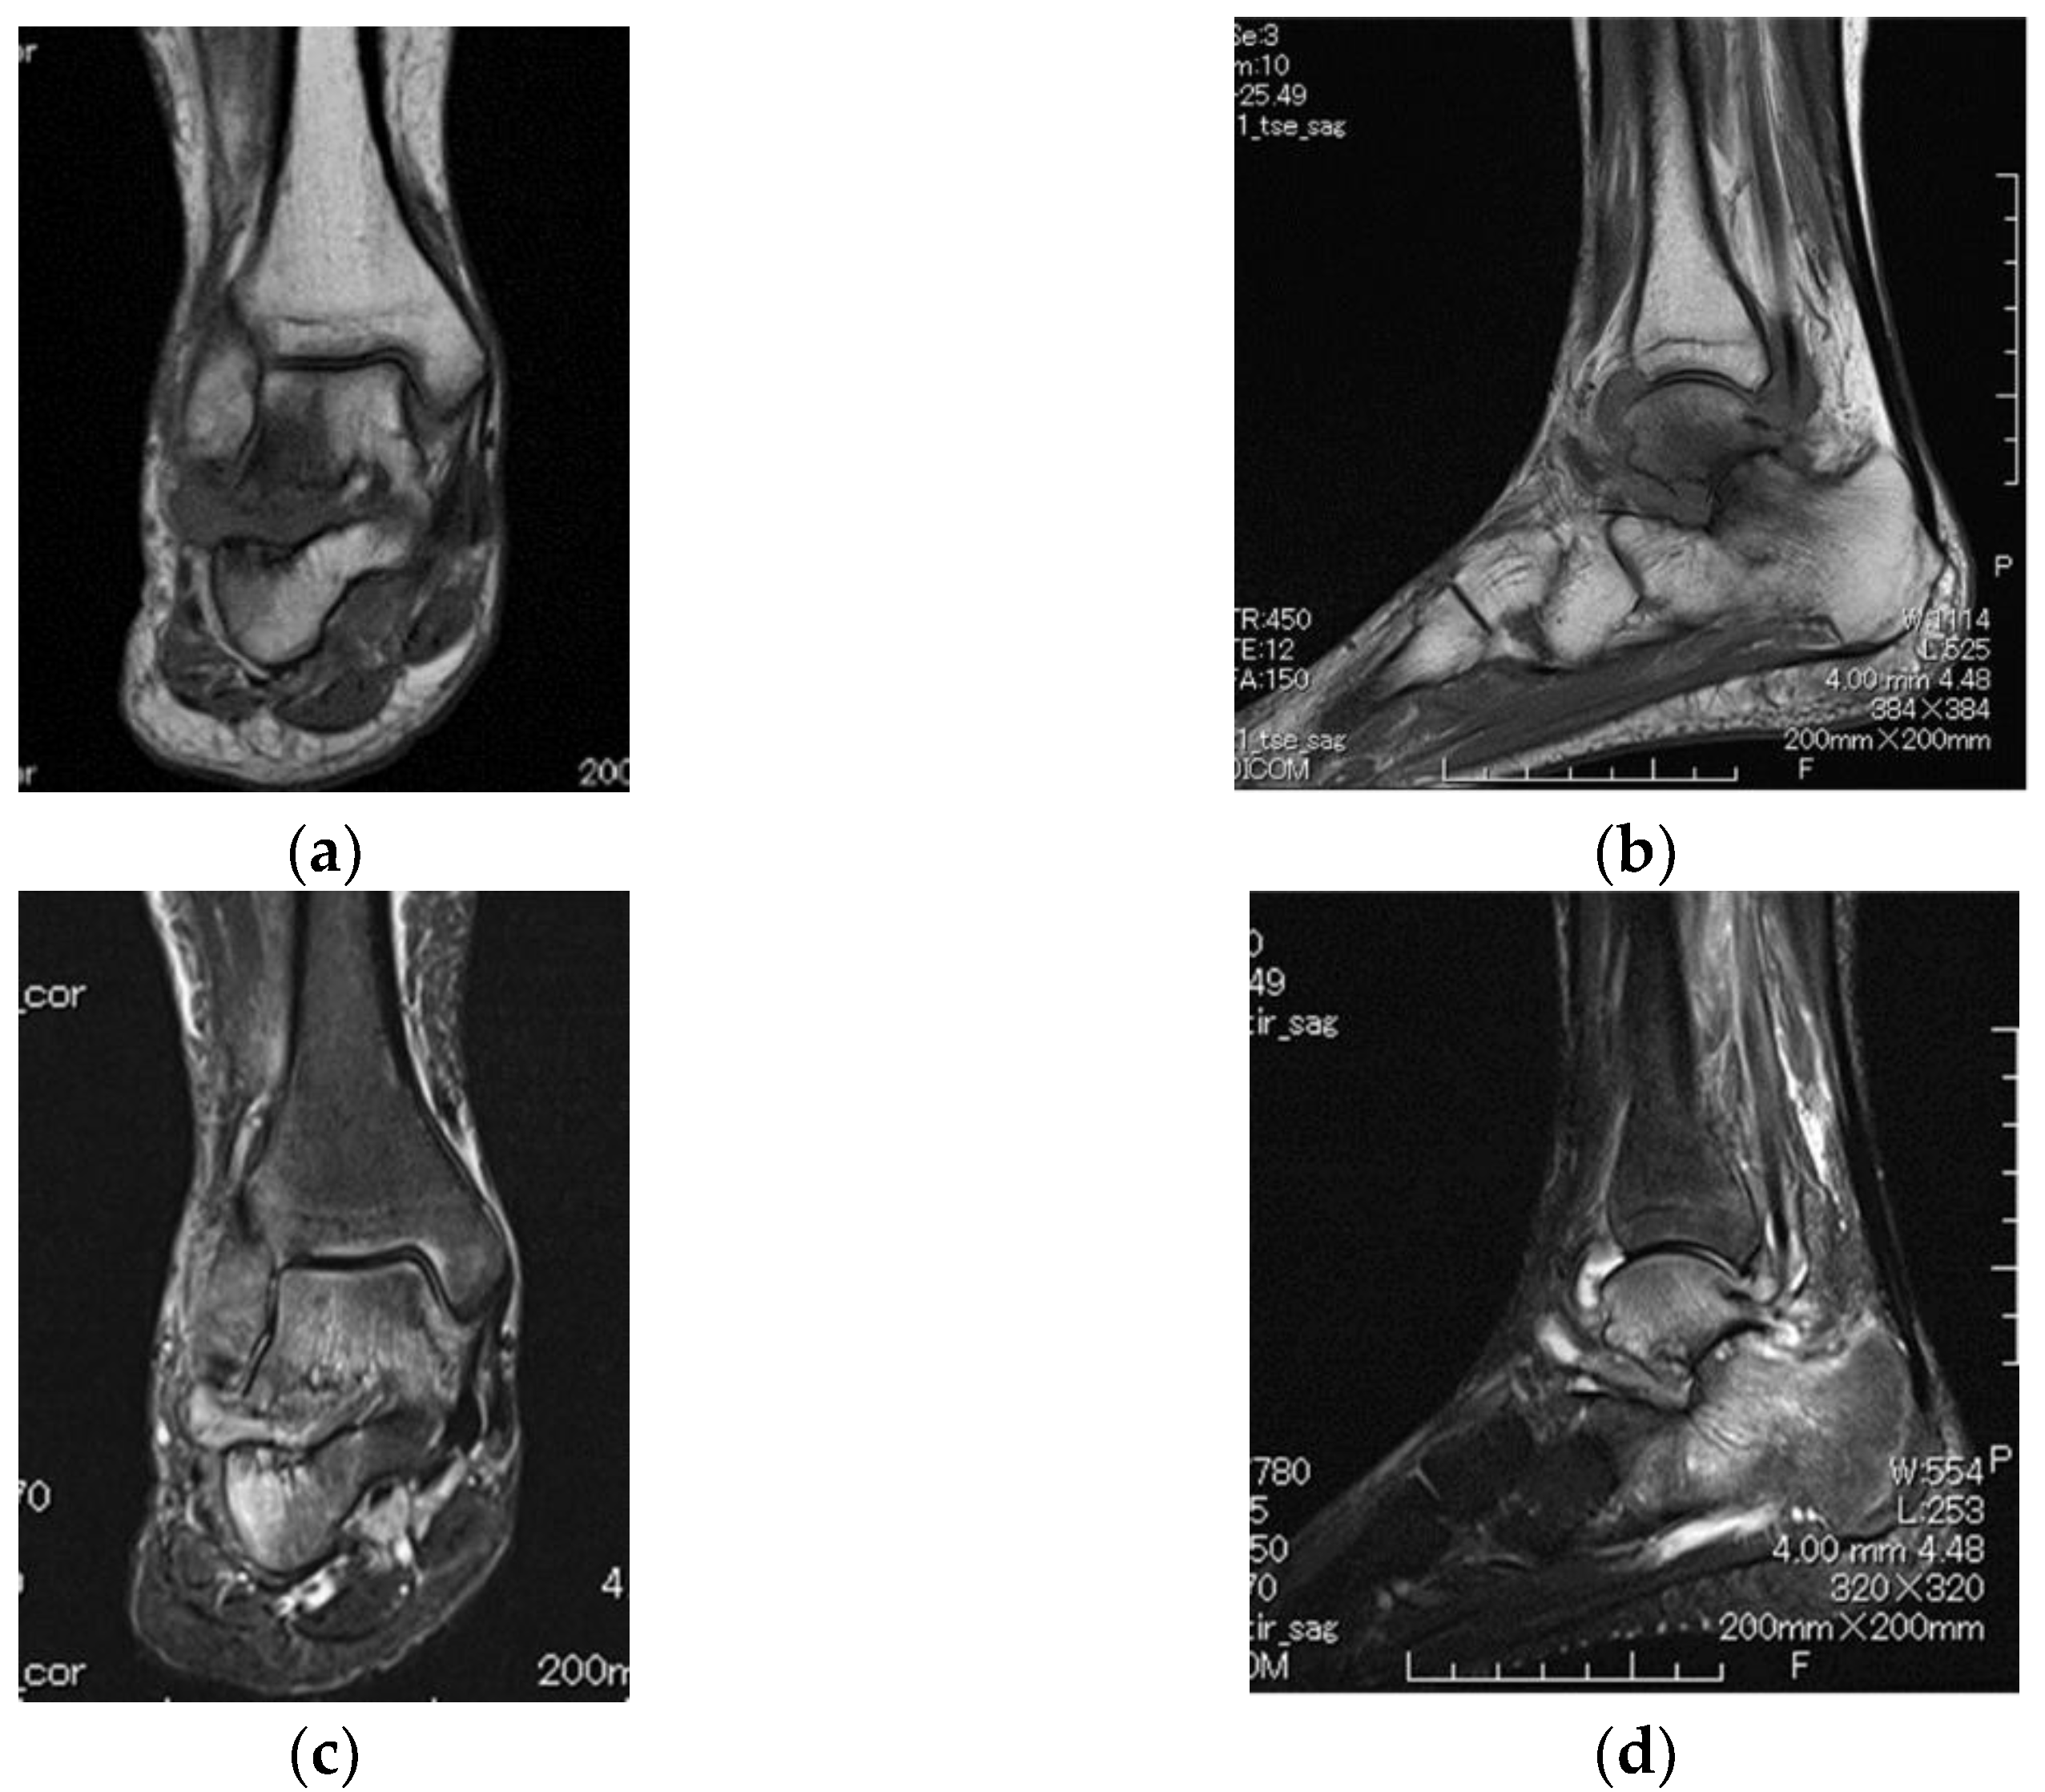

2. Case Presentation